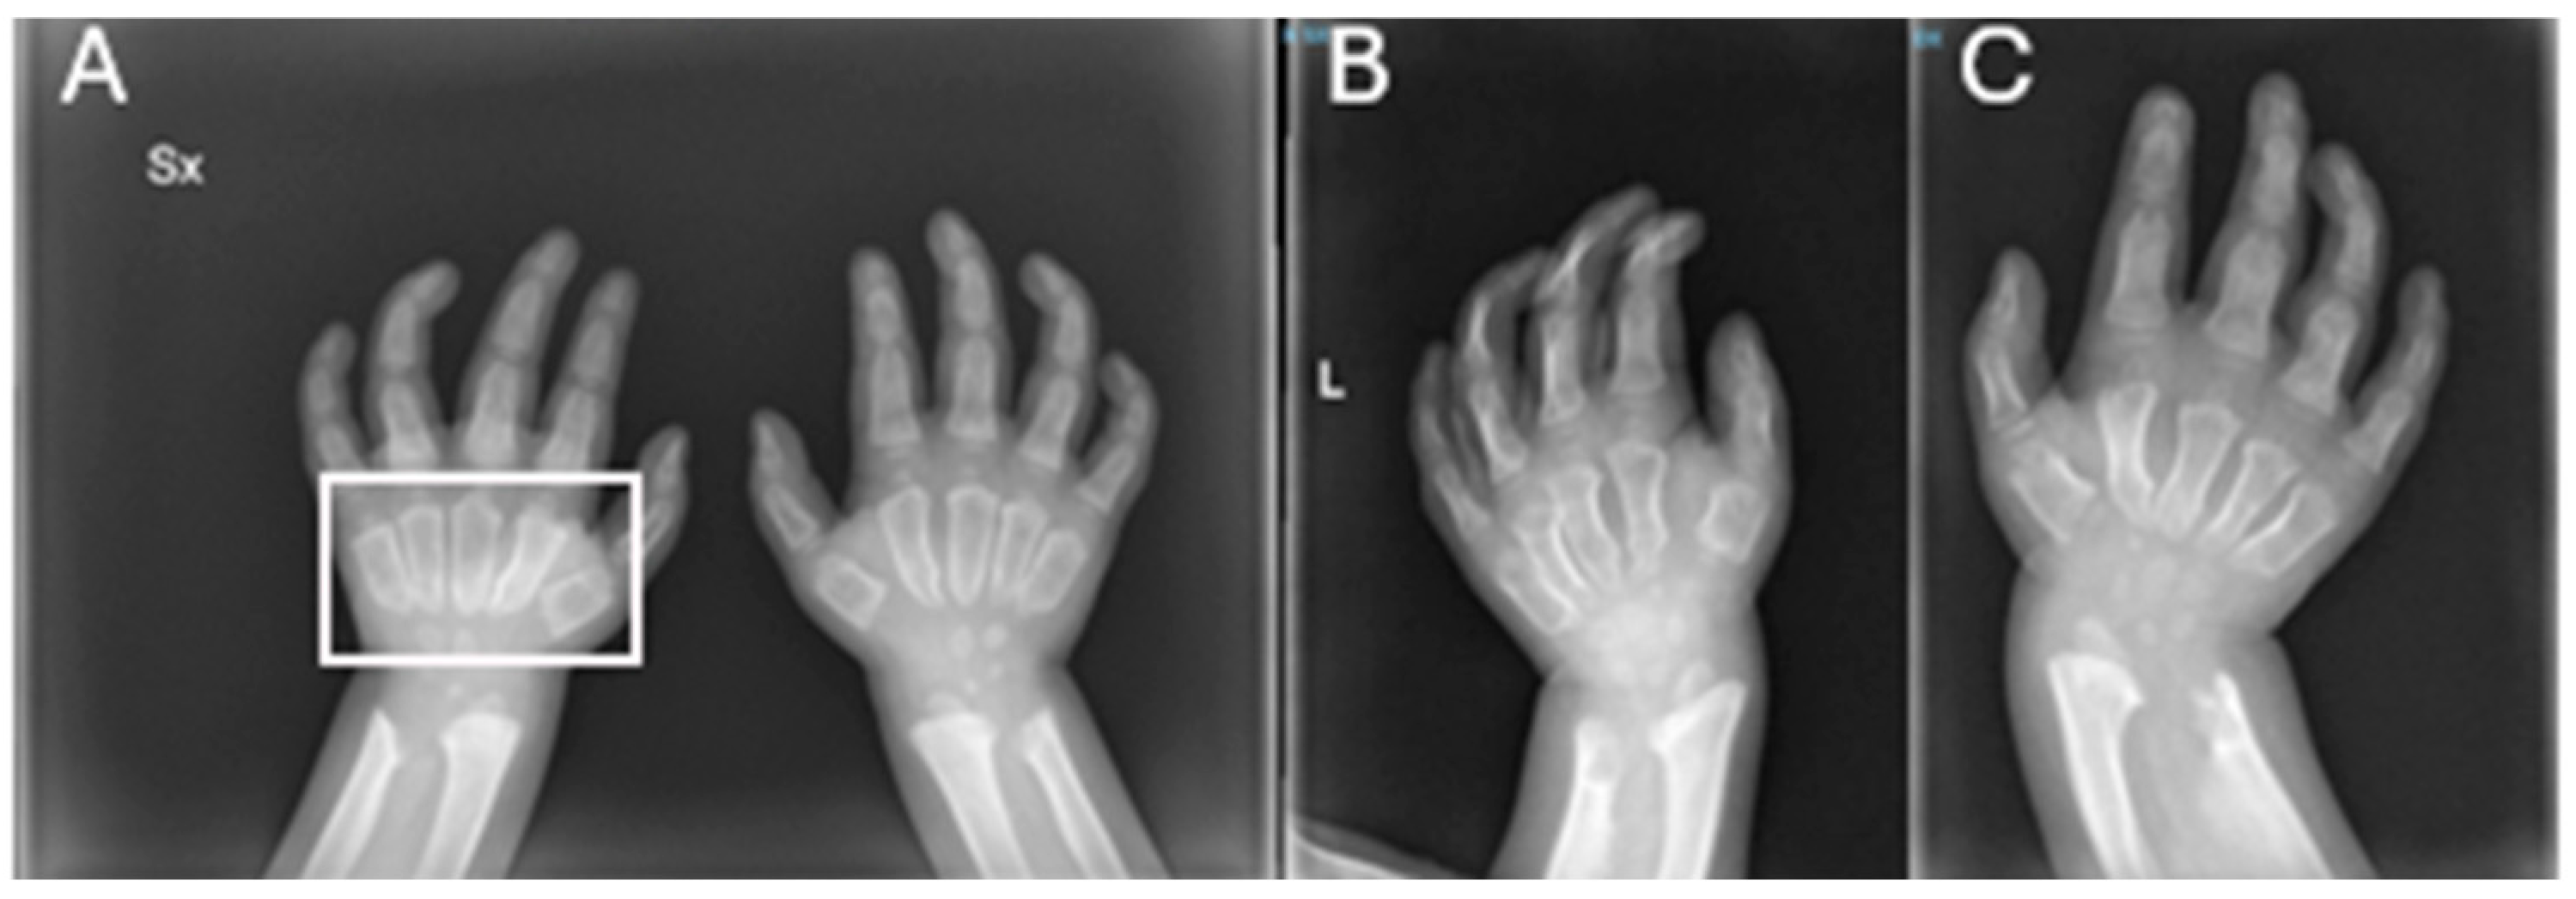

| RX | Hands | Short, thickened metacarpal bones; tapered proximal ends. | ||

| RX | Hands | Progression of the metacarpal deformities; malformative aspects of radius and ulna. | ||